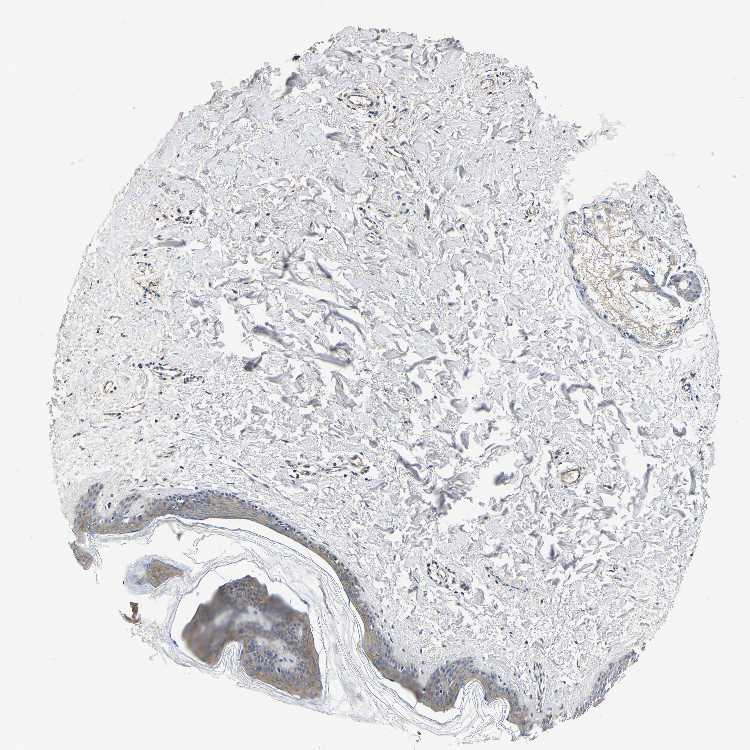

TISSUE PRIMARY DATA SKIN Show tissue menu

SKIN 1 - Antibody stainingi

Antibody staining in the annotated cell types in the current human tissue is reported as not detected, low, medium, or high, based on conventional immunohistochemistry profiling in selected tissues. This score is based on the combination of the staining intensity and fraction of stained cells.

Each image is clickable and will lead to virtual microscopy that enables deeper exploration of all samples and also displays staining intensity scores, fraction scores and subcellular localization as well as patient and tissue information for each sample.

Antibody HPA015608Antibody HPA019900Antibody CAB004650

Langerhans MediumMediumMedium

Fibroblasts MediumMediumNot detected

Keratinocytes MediumMediumMedium

Melanocytes MediumMediumLow

SKIN 2 - Antibody stainingi

Epidermal cells MediumNot detectedMedium